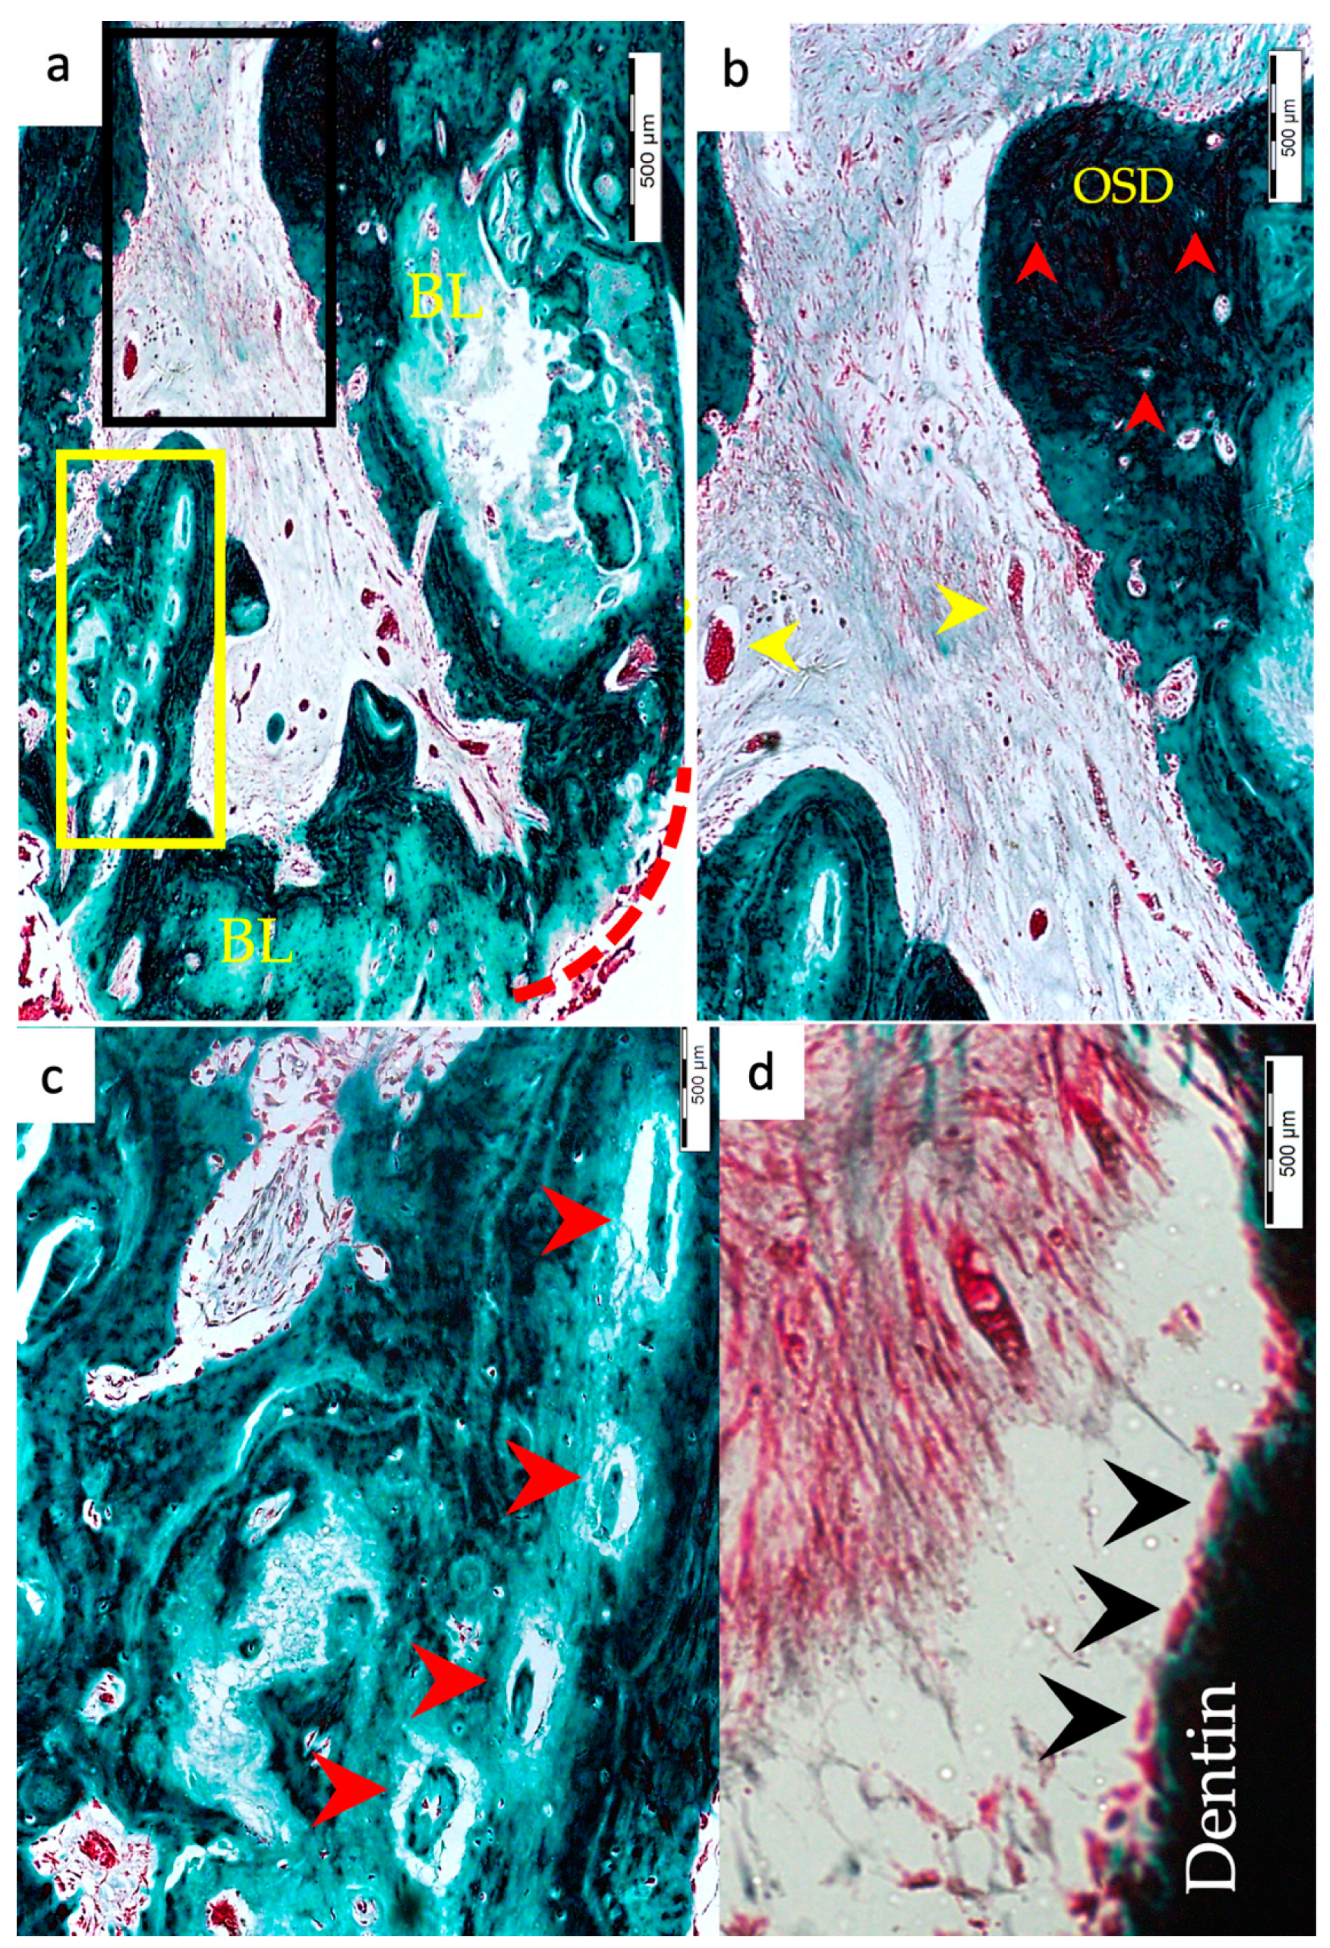

3.2. Type of Hard Tissue Formed

3.5. Apical Closure

3.6. Positive and Negative Control Groups